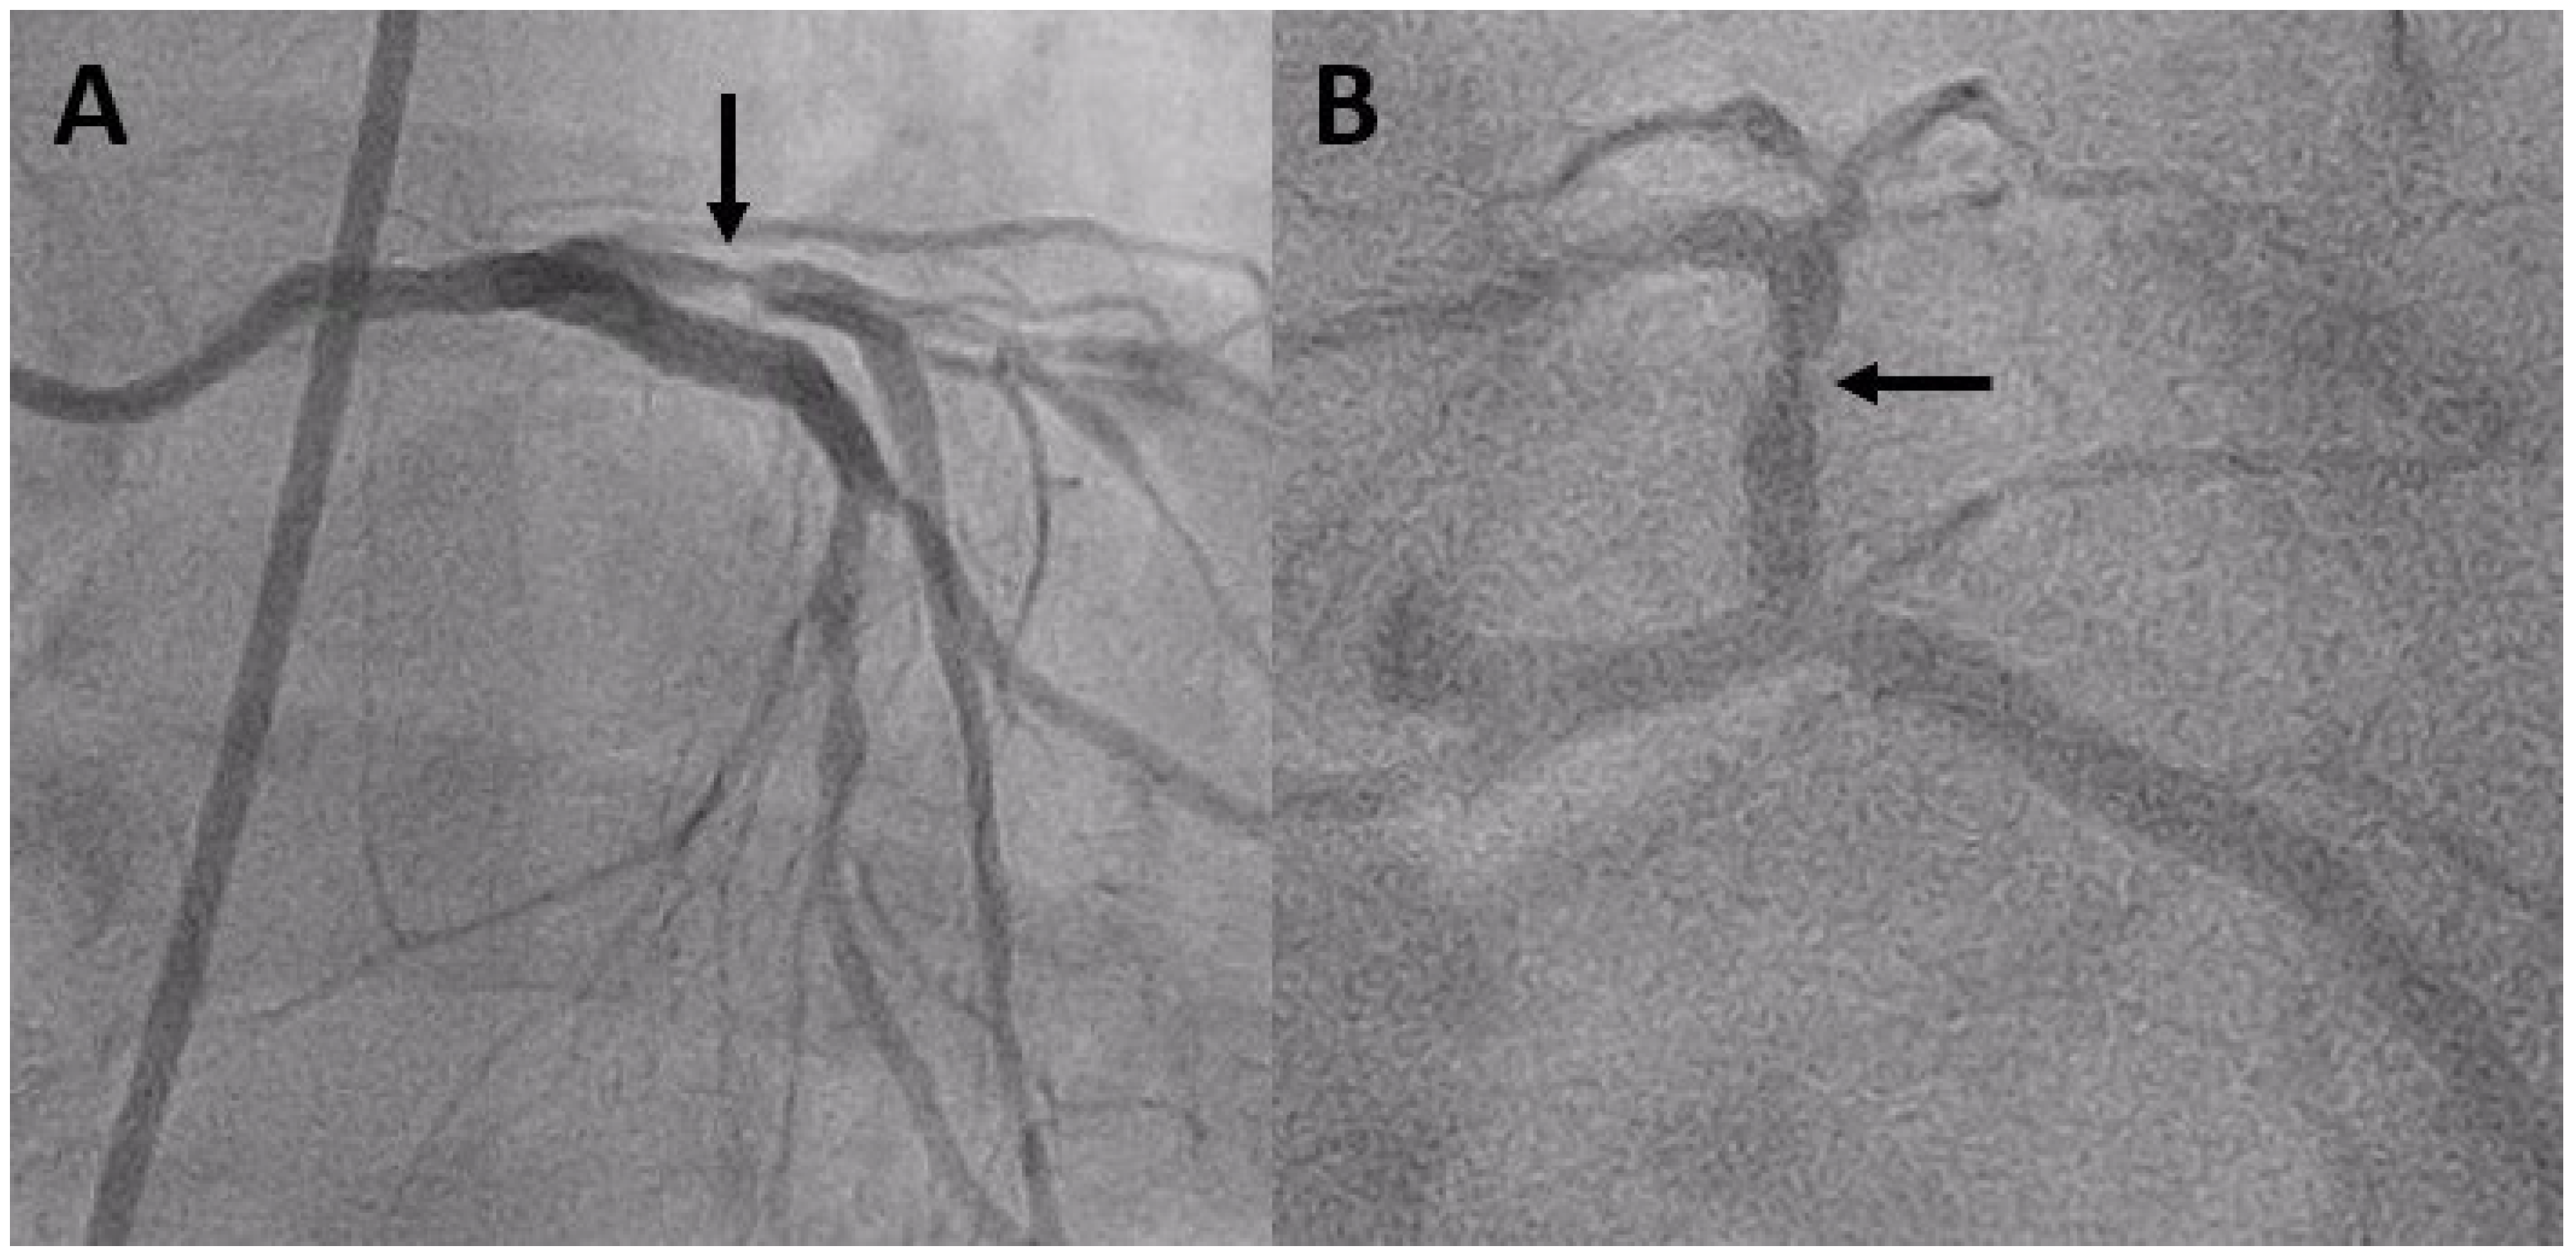

Coronary angiography on April 27, 2023, revealed severe ISR of the proximal LAD (Figure 1). A 60-MHz high-definition IVUS was performed, which revealed a homogenous echolucent appearance at an ISR of the SES (Figure 2A) and a suspected BH phenomenon.

Figure 1. A and B Coronary angiography showed a severe stenosis (black arrow) at the proximal portion of LAD.